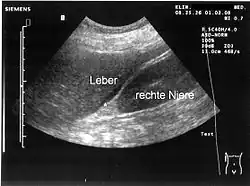

- Sonografie (Ultraschall): Geringe Mengen von Aszites lassen sich dabei am ehesten am Unterrand der Leber oder knapp oberhalb der Harnblase nachweisen. Der Raum zwischen Leber und Niere (Morison-Grube oder Recessus hepatorenalis) ist im Liegen der tiefste Punkt des Oberbauchs.